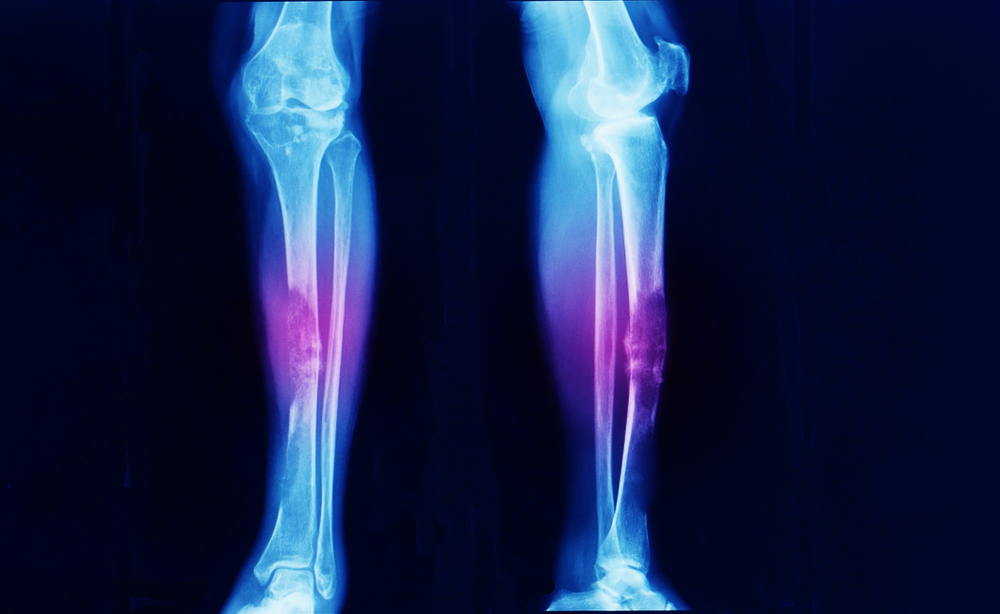

Kabilang ang bone cancer sa iba’t ibang uri ng cancer na nabubuo sa mga buto. Kapag tumubo ang mga cancer cells sa buto, maaari itong makapinsala sa normal tissue ng buto. Ang uri ng cell at tissue kung saan nagsisimula ang kanser ay tumutukoy sa uri ng cancer sa buto.

Tinatawag na primary bone cancer ang mga cancer na nabubuo sa mismong mga buto. Karaniwang naaapektuhang ang pelvis at ang mga mahahabang buto tulad ng mga braso at binti. Sa kabilan banda, ito naman ay tinatawag na secondary o metastatic bone cancer kung ang mga tumor ay nagsisimula sa mga organs o iba pang parte ng katawan at kalaunan kumakalat sa mga buto. Ang mga breast, prostate, at lung tumors ang karaniwang klase na lumalaganap sa mga buto.

Mayroong iba’t ibang uri ng pangunahing cancer sa buto. Ang mga senyales at sintomas ay pangunahing nakasalalay sa uri, lokasyon, at lawak ng cancer.

Osteosarcoma (Osteogenic Sarcoma)

Ito ang pinakakaraniwang uri ng canser sa buto na nangyayari sa mga cells kung saan nabubuo ang bagong tissue ng buto. Kadalasan itong nangyayari sa mga kabataan sa pagitan ng edad na 10 at 30. Ngunit, humigit-kumulang 1 sa 10 osteosarcomas ang nabubuo sa mga taong mas matanda sa 60. Ito ay bihira sa mga middle-aged na tao, at mas karaniwan sa mga lalaki kaysa sa mga babae. Katulad ng nabanggit, ang mga tumor para sa naturang uri ay kadalasang nabubuo sa mga buto ng mga braso, binti, o pelvis.

Ewing Sarcoma (Ewing Tumor)

Ang sunod na karaniwang uri naman ay kinikilalang Ewing sarcoma o tumor. Maaaring mabuo ang mga tumor sa mga buto at sa mga nakapalibot na malalambot na tissue. Madalas ito nangyayari at lumalaki sa balakang, tadyang (ribs), shoulder blades, o mga binti.

Makatutulong ang mga imaging tests upang matukoy at masuri ang lokasyon at laki ng tumor, at kung kumalat na ito sa ibang bahagi ng katawan. Karaniwang isinasagawa ang bone scan, computerized tomography (CT), magnetic resonance imaging (MRI), positron emission tomography, at x-ray.